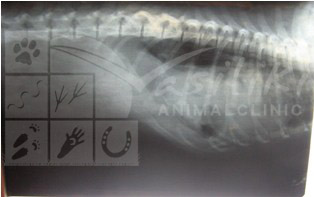

Έγινε ακτινογραφία θώρακος όπου διαπιστώθηκε ότι ο Λάκης είχε υποστεί έναν σοβαρότατο τραυματισμό , πιθανότατα από αυτοκίνητο, και είχε υποστεί ρήξη του διαφράγματος. Σαν αποτέλεσμα, μέρος των ενδοκοιλιακών του οργάνων ( συκώτι, στομάχι, εντερικές έλικες) είχαν εισέλθει στον θώρακά του και δυσκόλευαν την αναπνοή και καρδιακή λειτουργία του.

ΑΚΤΙΝΟΓΡΑΦΙΕΣ ΠΡΙΝ ΚΑΙ ΜΕΤΑ ΤΗΝ ΕΠΕΜΒΑΣΗ

ΠΡΙΝ